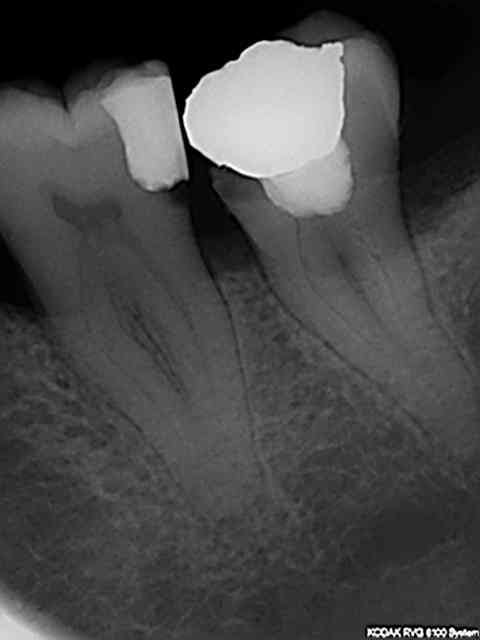

Remarque c'est pas con la tracabilité. Par exemple j'aimerais bien connaitre le nom du praticien qui a fait ce magnifique traitement endo pour savoir quel matériau il a utilisé car il a l'air d'etre très efficace; meme pas de peche !

R26 hsgjsd - Eugenol

R5 d0bnab - Eugenol